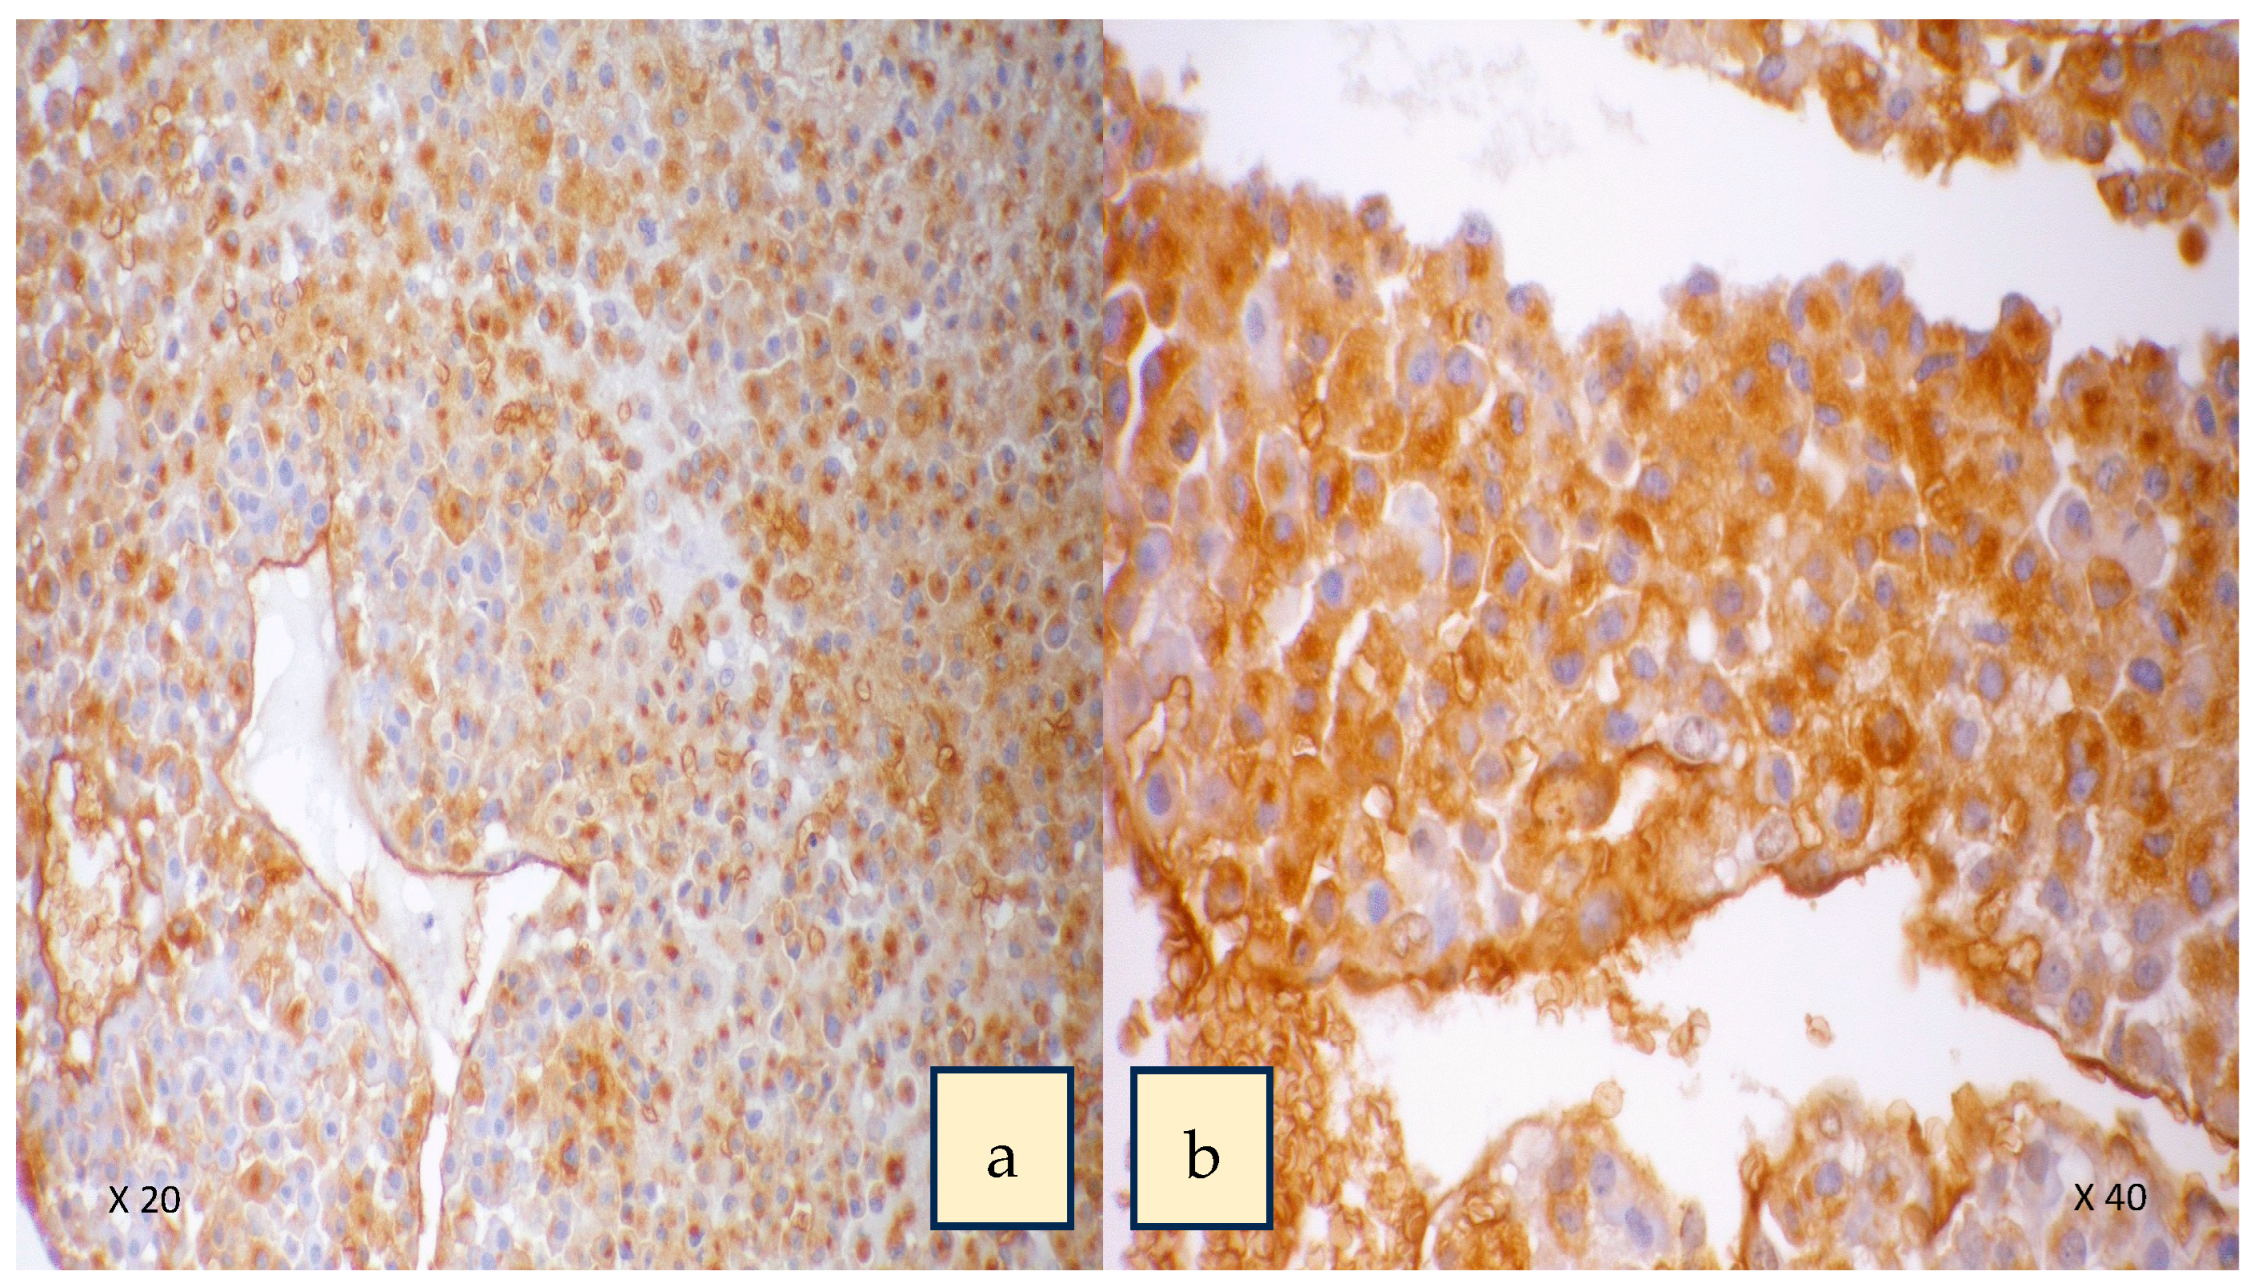

A two-centre study of 32 patients treated with surgery for adrenocortical carcinoma that was evaluated with lectin histochemistry of the cancers excised showed that expression of HPA binding truncated O-glycans was associated with invasive characteristics and poorer survival (Figure 3) [36]. Patients with positive HPA labelling had a mean survival of 22 months with a mortality rate of 84% versus negative HPA labelling with a mortality rate of 23% [36]. Labelling was seen along the cell surface and cytoplasm in the cancer cells, similar to that observed in thyroid and breast cancer [94,100] (Figure 4). In the study, positive HPA labelling did not correlate with metastasis, unlike the studies in breast and colon cancer, where the HPA binding partners of integrin α5 and α6 and annexin 2 and 4 were found to play a key role [106,107]. The exact binding partners were not identified in the ACC study as it required characterization using affinity chromatography and mass spectrometry using fresh tumour samples that were not available for the cohort.

Figure 4.

HPA labelling showing intense staining in cytoplasm and cell surface of the cancer cells in adrenocortical carcinoma. Panel (a) high-power 20× magnification. Panel (b) 40× magnification. Used with permission from Parameswaran et al. [36].